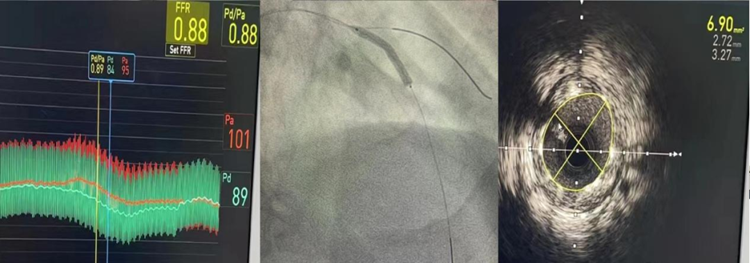

植入支架后,FFR 0.88,最小支架面积6.9平方毫米